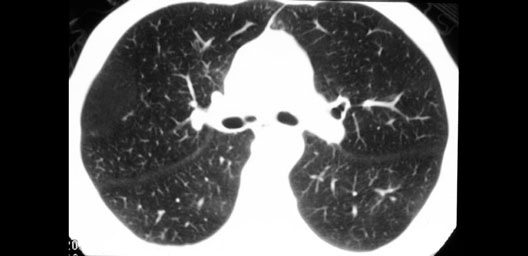

Trachea Bifurcation

1. Cardiac bronchus (normal variation)

2. Right middle lobe

3. Right main bronchus

4. Right oblique fissure

5. Right lower lobe

6. Lingular lobe of the left lung

7. Left upper lobe

8. Left upper lobe bronchus

9. Left main bronchus

10. Left oblique fissure

11. Left lower lobe